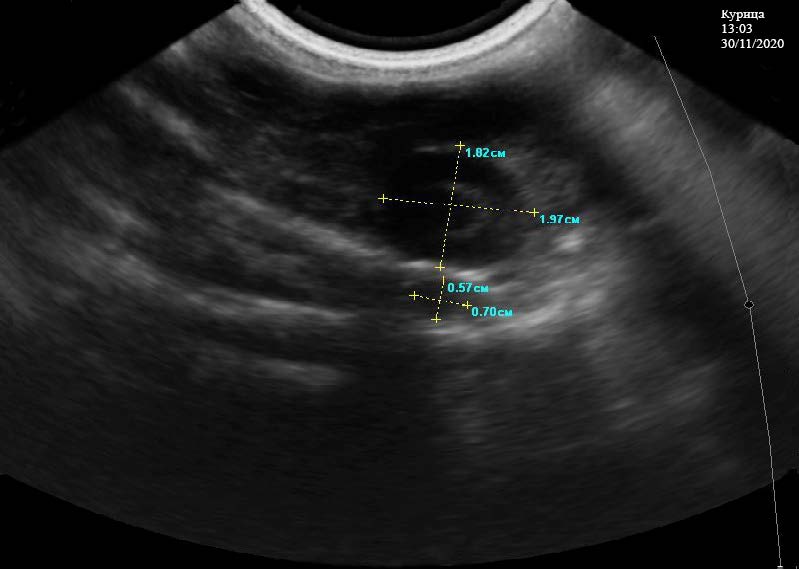

Третий этап исследование проводили в 13:03 часов 30.11.2020. Желток расположен в каудальной части белкового отдела, имеет размеры 0,68*0,81 см. Отмечается его большая плотность, хорошая эхогенность. На его периферии располагается белок с несколькими слоями, имеющий размеры 1,97*1,82 см и 0,57*0,70 см. Отмечается низкая плотность белка и эхогенная структура гиперэхогенного характера со слабой акустической тенью.

Белковый отдел смещен несколько влево, имеет сильно извитые петли. Границы яйцевода хорошо контурированы. Стенка белкового отдела хорошо структурирована, выраженность слоев отмечается слабо. Толщина стенок равномерная, соответствует ультразвуковой норме. В полости яйцевода отмечается содержимое однородной структуры со незначительным количеством содержимого жидкой консистенции. Перистальтика белкового отдела сохранена (рис. 4).

Рис. 4. Средняя часть белкового отдела у курицы кросс «Хайсекс белый», с наличием желтка с увеличенной массой белка. 13:03 ч. 30.11.2020 г.